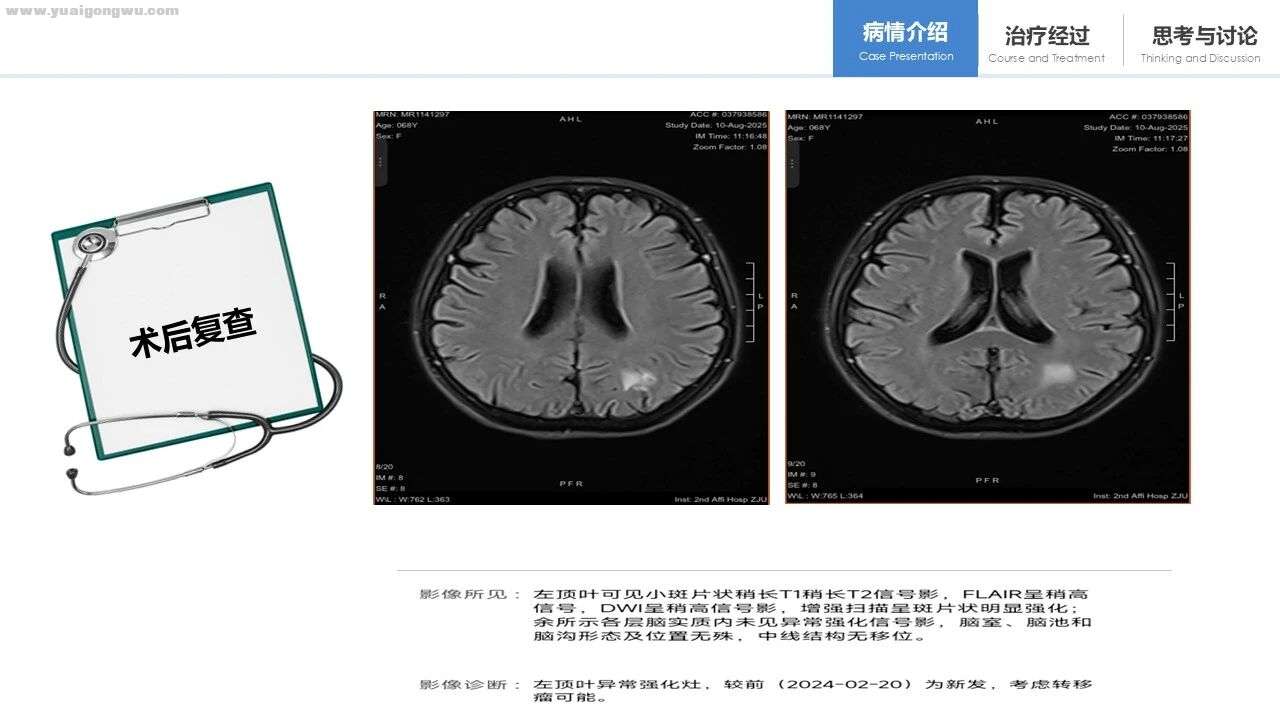

李成海教授 该患者2022年10月体检行胸部CT(未提供片子),报告显示右肺中叶肺门旁有2.5×2.9cm结节,当时考虑恶性可能性大,后续手术证实该判断。淋巴结方面,因未看到相关影像,仅知术中取了几组淋巴结且部分异常。患者术后接受治疗,2025年头部CT提示左侧顶叶强化灶,结合病史诊断为转移灶,结论无误。对比后续胸部CT,4L区淋巴结较前增大,转移可能性明确;右肺门处淋巴结参考影像也略有增大,推测大概率存在转移。

不过,如病理科此前所说,该患者肿瘤分化程度较低,且存在特定突变。尽管患者随访规律,但在今年8月仍发现影像学异常。通常情况下,当患者术后出现影像学异常时,需通过组织学病理检查明确是否为真正复发,不过该患者因多种原因未能或无法进行组织活检。目前患者已接受规范的局部放疗,涵盖头部与胸部,但从病情来看,仍有必要开展全身治疗,一方面基于患者的病理情况,另一方面患者术后分期较晚,且较快出现转移,因此全身治疗的必要性较为突出,具体方案需结合患者的实际诉求确定。